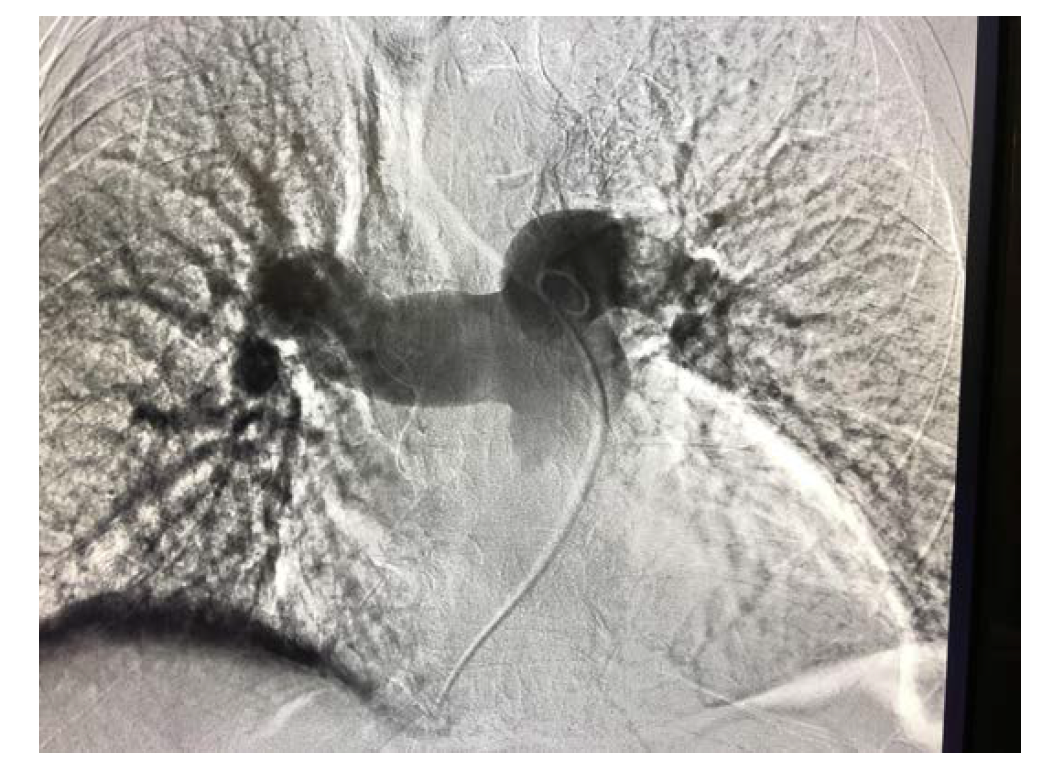

There were procedural differences between interventional cardiology and interventional radiology techniques for CDT. While Interventional radiology used the traditional femoral vein approach for the 3 cases performed by them, interventional cardiology used the internal jugular vein, brachial vein, and basilic vein approaches, in addition to conventional femoral access. All the patients had two catheters placed in every case of bilateral PE. The duration of alteplase (tPA) differed among the cases, as summarized in Table 3, and the mean total duration of tPA was 23.5 mg. In 11 of the 12 cases, heparin was used along with tPA at a reduced dose. Details of CDT and complications of each case are summarized in Table 3, and a fluoroscopic image of the procedure is depicted in Figure 1.